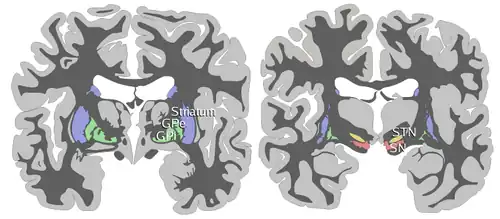

Au sens fonctionnel, on aborde ces structures de manière différente :

- le striatum composé du noyau caudé et du putamen (correspondant à la partie latérale du noyau lenticulaire) ;

- le globus pallidus interne (GPi) et le globus pallidus externe (GPe), correspondant au pallidum (partie médiale du noyau lenticulaire) ;

- le noyau sous-thalamique (ou corps de Luys) ;

- la substance noire compacte (SNpc, du latin : substantia nigra pars compacta), et la substance noire réticulée (SNr, substantia nigra pars reticulata).

Le striatum, le GPe, le GPi et la SNpr sont essentiellement composés de neurones inhibiteurs (gabaergiques), dans le circuit, seul le noyau subthalamique est composé de neurones excitateurs (glutamatergiques).

Les interconnexions des différents noyaux des ganglions de la base sont assez complexes. Le striatum et le noyau subthalamique reçoivent des entrées du cortex, le GPi et la SNr sont les sorties du circuit, qui projettent sur le thalamus. L'intérieur du circuit est composé de projections inhibitrices du striatum vers le GPe, le GPi et la SNr ; de projections excitatrices du noyau subthalamique vers le striatum, le GPe, le GPi et la SNr ; de projections inhibitrices du GPe vers le striatum, le noyau subthalamique, le GPi et la SNr. Une interprétation de cette connectivité en termes de chemins (ou voies) dits direct et indirect a été proposée pour expliquer les troubles moteurs apparaissant en particulier dans la maladie de Parkinson[3]: